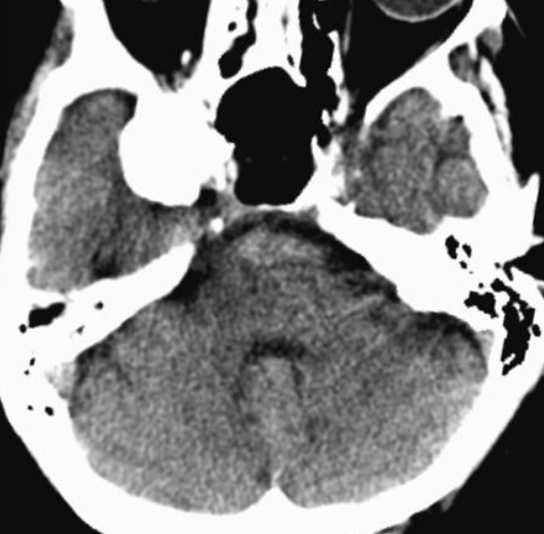

Note the multiple sites of oedema and haemorrhage, involving the brain stem and corpus callosum as well as subcortical white matter and left cerebral peduncle. High FLAIR signal is also seen in the dorsal midbrain. EVD insitu.

Case Discussion

Diffuse axonal injury can be subtle on CT but have devastating consequences for the patient. This is a case of grade III injury (involvement of brainstem) and carries a poor prognosis.

Diffuse axonal injury (DAI), also known as traumatic axonal injury (TAI), is a severe form of traumatic brain injury due to shearing forces. It is a potentially difficult diagnosis to make on imaging alone, especially on CT as the finding can be subtle, however, it has the potential to result in severe neurological impairment.

CT

Non-contrast CT of the brain is routine in patients presenting with head injuries. Unfortunately, it is not sensitive to subtle diffuse axonal injury and as such, some patients with relatively normal CT scans may have significant unexplained neurological deficit 4,5.

The appearance depends on whether or not the lesions are overtly haemorrhagic. Haemorrhagic lesions will be hyperdense and range in size from a few millimetres to a few centimetres in diameter. Non-haemorrhagic lesions are hypodense. They typically become more evident over the first few days as oedema develops around them. They may be associated with significant and disproportionate cerebral swelling.

CT is particularly insensitive to non-haemorrhagic lesions (as defined by CT) only able to detect 19% of such lesions, compared to 92% using T2 weighted imaging 4. When lesions are haemorrhagic, and especially when they are large, then CT is quite sensitive. As such, it is usually a safe assumption that if a couple of small haemorrhagic lesions are visible on CT, the degree of damage is much greater.